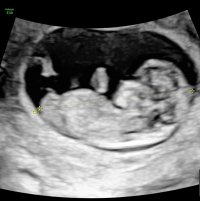

Her kan man legge ut bilder fra tidlig ultralyd og gjette hverandres kjønn.

Nub er hva man kaller barnets kjønnsorgan. Man kan se forskjell på hvilken vinkel den står i. Jenter har gjerne lang flat nub som går rett frem. Gutter har nub som står mer opp og har også ofte det man kaller "stacking". Ser ut som en ball oppå nub.

Bildene må være fra uke 12 og utover. Barnet bør ligge i sideprofil. Husk å skrive hvilken uke+dag bildet er tatt.

Nub teorien er hva ultralydteknikere også vurderer kjønn på før man kan se pung og kjønnslepper. Så har man et godt bilde så vil man kunne se kjønn lenge før oul.